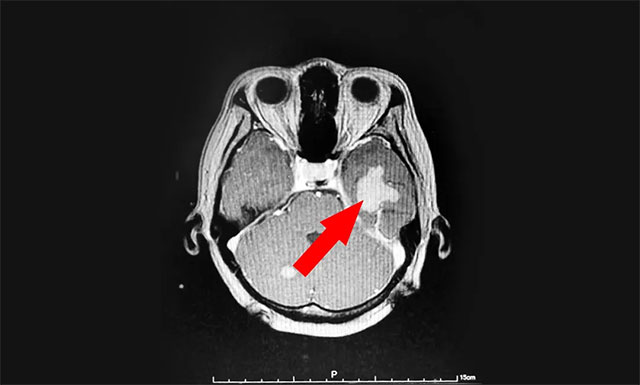

今年43歲的患者湯女士(化名),于2020年8月因頭暈伴體倦乏力至當(dāng)?shù)蒯t(yī)院就診,查體PET-CT:右肺上葉前段結(jié)節(jié),考慮周圍型肺癌。右肺門、縱膈多發(fā)淋巴結(jié)轉(zhuǎn)移,顱內(nèi)多發(fā)轉(zhuǎn)移。湯女士在外院接受放射治療后,頭暈乏力等癥狀得到了一定的改善。

▲ 來藍(lán)十字治療前患者的囊性轉(zhuǎn)移瘤病灶

近期,患者為尋求進(jìn)一步治療,來到上海藍(lán)十字腦科醫(yī)院。醫(yī)院腫瘤科(放療)頭部伽瑪?shù)督M主任陳琦及醫(yī)生團(tuán)隊結(jié)合患者病情變化,為湯女士行立體定向穿刺引流聯(lián)合伽瑪?shù)吨委。?jīng)一段時間住院恢復(fù)后復(fù)查,病灶占位較前進(jìn)一步縮小,腫瘤進(jìn)展得到了較好地控制,目前已順利出院。

▲ 伽瑪?shù)吨委熀髲?fù)查,可見病灶占位明顯縮小